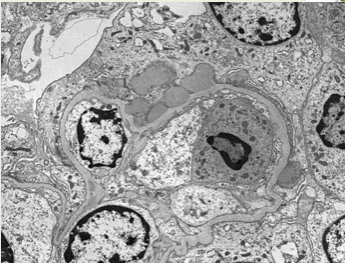

Post Infectious EM

• Usually nephrotoxic strep, usually self-resolves

• ICs and planted bacterial antigens cause activation of alternative complement pathway

• Diffuse glomerular hypercellularity

• Prolif of endothelial and mesangial cells

• Infiltration of neutrophils and monocytes

• => Occlusion of capillaries

• EM: Subepithelial humps due to non-uniformly placed immune deposits into the sub-epithelial space